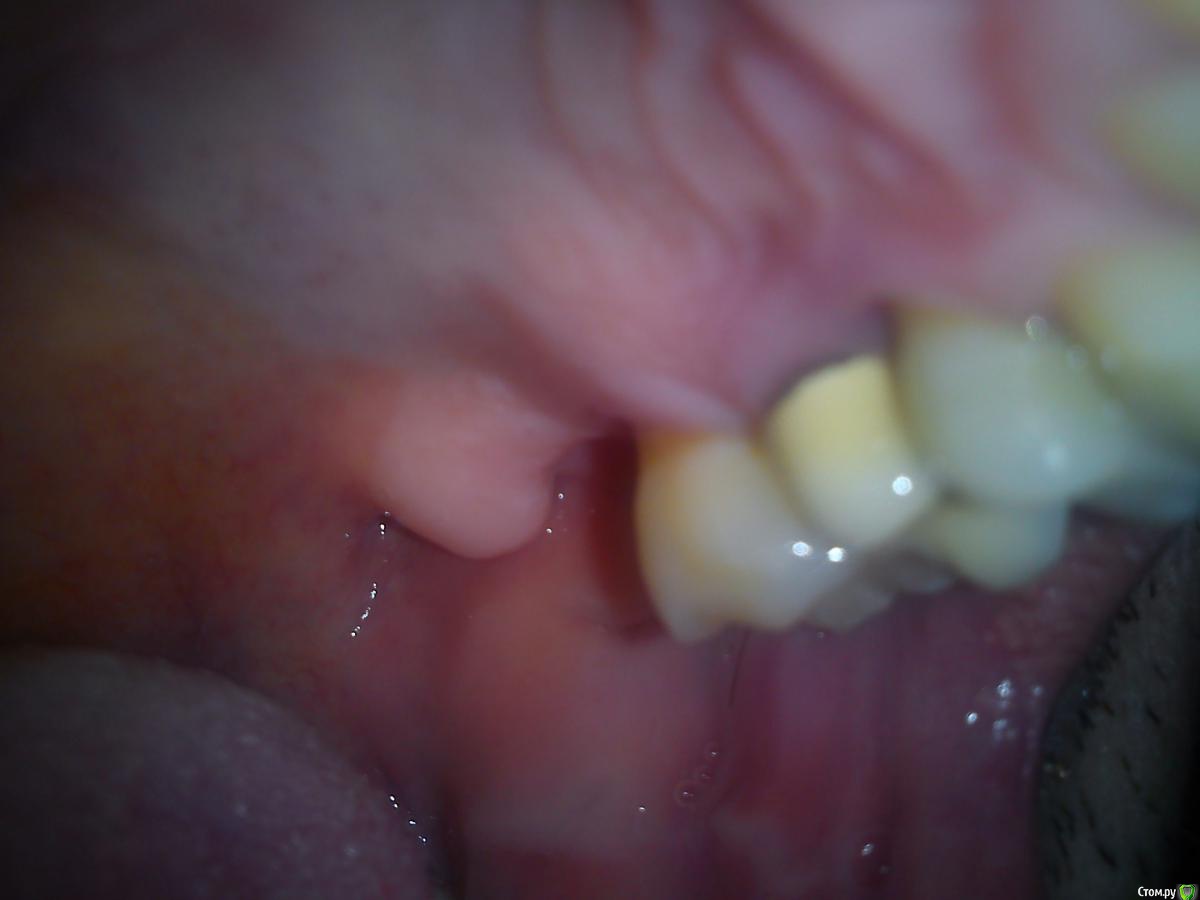

Макс111 Опубликовано 16 декабря, 2015 Поделиться Опубликовано 16 декабря, 2015 Добрый день!По возможности, прошу посмотреть мою КТ. Правда, не разобрался какую именно папку выкладывать, поэтомувот тут ссылка только на папку с файлами с расширением .DCM https://yadi.sk/d/NQrtBNRKmFtRC А вот тут на все содержимое диска вместе с программой для просмотра, на всякий случай:https://yadi.sk/d/O5yoL0QImFu3Y Так же к теме прикрепляю фото 24, 25 с внешней и внутренней стороны, а так же фото ниж ч там где 46 У меня пародонтит, и тд.В целом, вопрос по 24 и 25 зубу, между ними как видно большой карман. 25 это коронка на зубе, десна опустились и она полностью оголилась, видно уже корень , коронка на десной на пару мм. 24 это в общем то пломба огромная на весь зуб.Что можно сделать? Мне предлагают снять коронку, потом сделать лоскутную операцию, в ходе которой подсадить материал для формирования кости, чтоб уменьшить этот карман и потом сделать сделать коронку и на 25 и на 24 тоже коронку одеть.Какое ваше мнение по 24, 25? Как бы вы сделали, в какой очередности?27 и 28 потерял около 9 мес назад, над ними была киста, ее вырезали.А ну и плюс хронический гайморит. Так же прошу посмотреть в низу 46 зуб, можно ли туда вкрутить имплант или предварительно регенерировать кость нужно? каким методом?у 7 ки там такая форма, что между зубами видимо будет пустота? Как с этим бороться? Когда там был зуб так и были и поэтому 46 портился, стояла пломба, но 3 месяца назад он раскололся, сохранить возможности не было, плюс была киста и его пришлось удалить..Стоит ли сразу удалить 48, чтоб он не давил на 47 или можно подождать пока верх сделаю, чтоб было чем есть пока? Спасибо, если кто то посмотрит! Ссылка на комментарий

Карен Аванесов Опубликовано 16 декабря, 2015 Поделиться Опубликовано 16 декабря, 2015 В области бифуркаций моляров да. Ссылка на комментарий